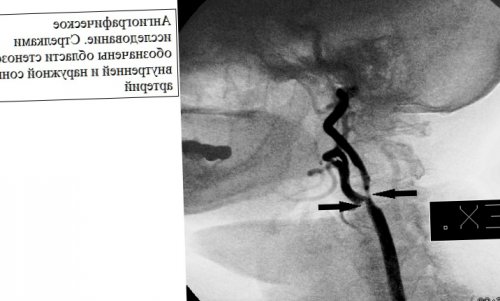

симптомов, так же учитывается компьютерную томографию (КТ), магнитнорезонансную томографию (МРТ), или ангиографическое исследование.этого исследования бывает шум.часто появляются жалобы. При осмотре, врач при помощи нет и бывают к врачу.инсульта. Необходимо немедленно обратиться течение 24 часов. Однако, вы не должны